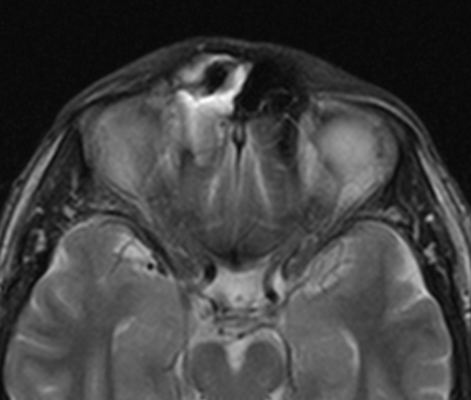

Пиоцеле (скопление гноя) задних клеток решетчатой кости